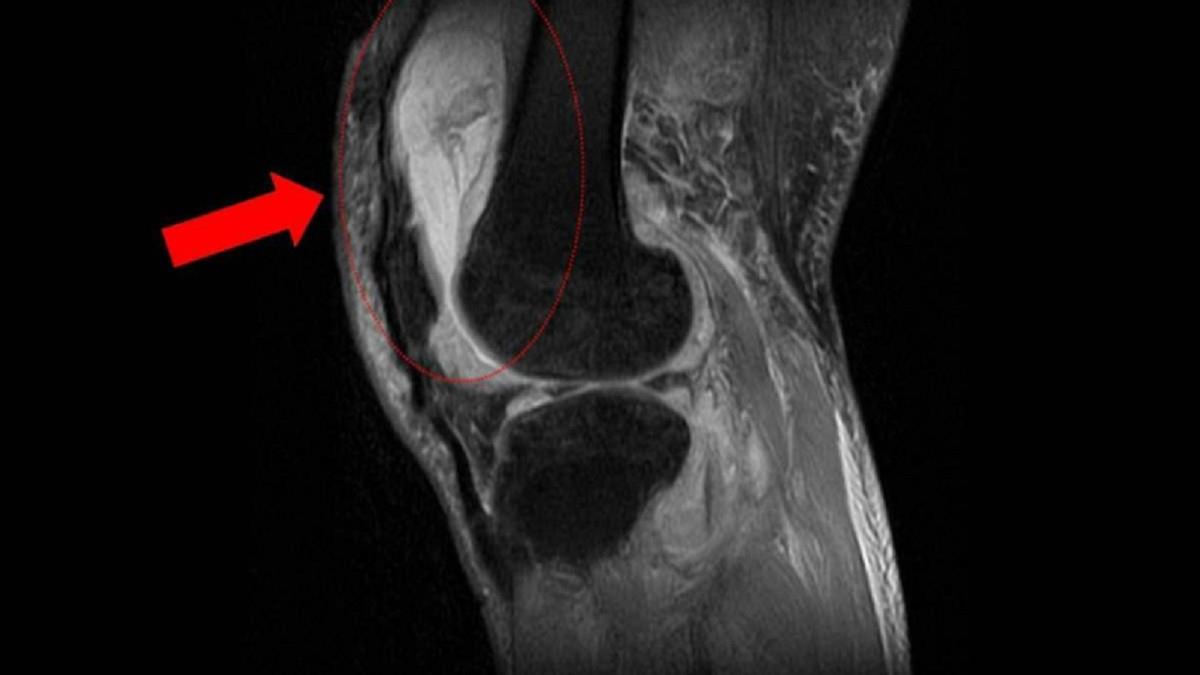

膝蓋腫到彎不了! 他吃止痛藥更嚴重 就醫驚見「骨化膿 」